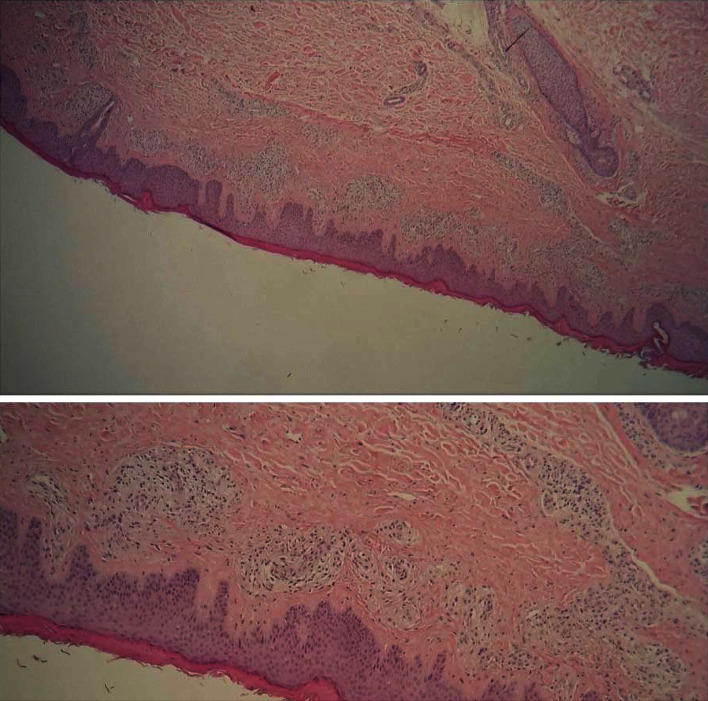

Reactive angioendotheliomatosis (RAE) is a rare benign skin condition characterized histologically by the proliferation of dermal vessels and endothelial cells that occurs secondary to an underlying disease such as infections or lymphoproliferative disorders. To our knowledge, no previous cases of RAE associated with ulcerative colitis (UC) were reported in the literature. Therefore, we report the case of a 46-year-old man with a history of UC presenting with RAE confirmed on histopathology and immunostaining.